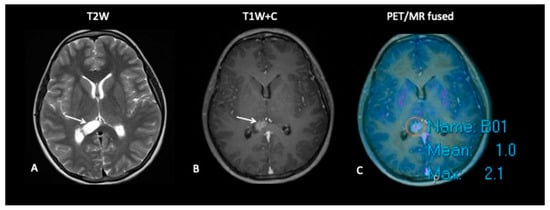

- Patient 8: Suspicion of Transformation

A 15-year-old female with known low-grade glioma during routine surveillance was noted to have developed a large lesion in the corpus callosum. This occurred 7 years after her initial diagnosis of an optic pathway tumour. The MRI scan raised the possibility of malignant transformation to high-grade glioma. FDOPA (Figure 11) discounted the possibility of transformation as the FDOPA uptake within the corpus callosal lesion was low intensity, unlike that seen in high-grade gliomas.

Figure 11.

MRI demonstrates an expansile lesion in the right aspect of the splenium (A), which demonstrates heterogenous enhancement (B), suspicious for malignant transformation. However, FDOPA (C) did not demonstrate increased uptake, and the lesion was considered low grade.